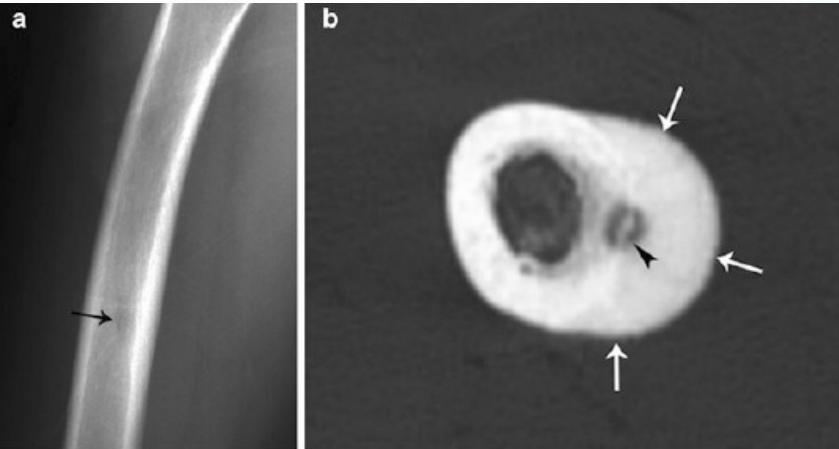

Non-Ossifying Fibroma

- Another name: Fibrous cortical defect

- The commonest benign lesion of bone

- Asymptomatic:

- Incidentally discovered

- Children:

- Disappears later

- Common site:

- Metaphysis of long bones

- Treatment:

- Observation

- Surgery if very large